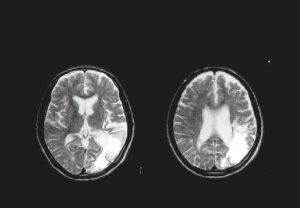

後方限局

後方限局病巣例

前方限局

前方限局病巣例

MCA広範病巣

広範病巣例